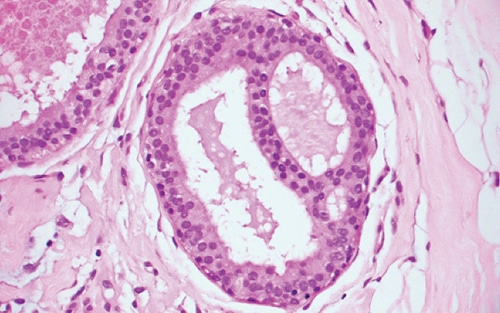

- UDH is identified when the ductal epithelium exceeds the normal one- to two-cell thickness, after accounting for tangential sectioning and other artifacts.

- Mild UDH is present when the ductal epithelium is up to four cells thick; on the other end of the spectrum, florid UDH fills duct lumens, while moderate UDH is between these extremes.

- The essential features of UDH, in contrast to DCIS and ADH, include cellular heterogeneity and architectural disorganization.

- The hyperplastic cellular population is cytologically heterogeneous and haphazardly arranged, with irregular cell spacing; the effect of this unevenness is luminal structures with rough, wavy borders and elongated, slit-like spaces (Figure 5-7).

- These slit-like spaces are typically found at the periphery of the duct lumen, with intervening epithelial “bridges” that are tapered rather than stout.

- Micropapillary UDH usually has broad-based elongated micropapillae with tapering ends (unlike ADH, which has narrow-based, short, bulbous micropapillae).

- The epithelium may appear spindled and “streaming,” particularly in “bridges” between adjacent spaces where the cells are generally aligned parallel to the lumen and may lay flat against it.

- Individual ductal epithelial cell nuclei are oval and frequently grooved. They have pale dispersed chromatin and small indistinct nucleoli.